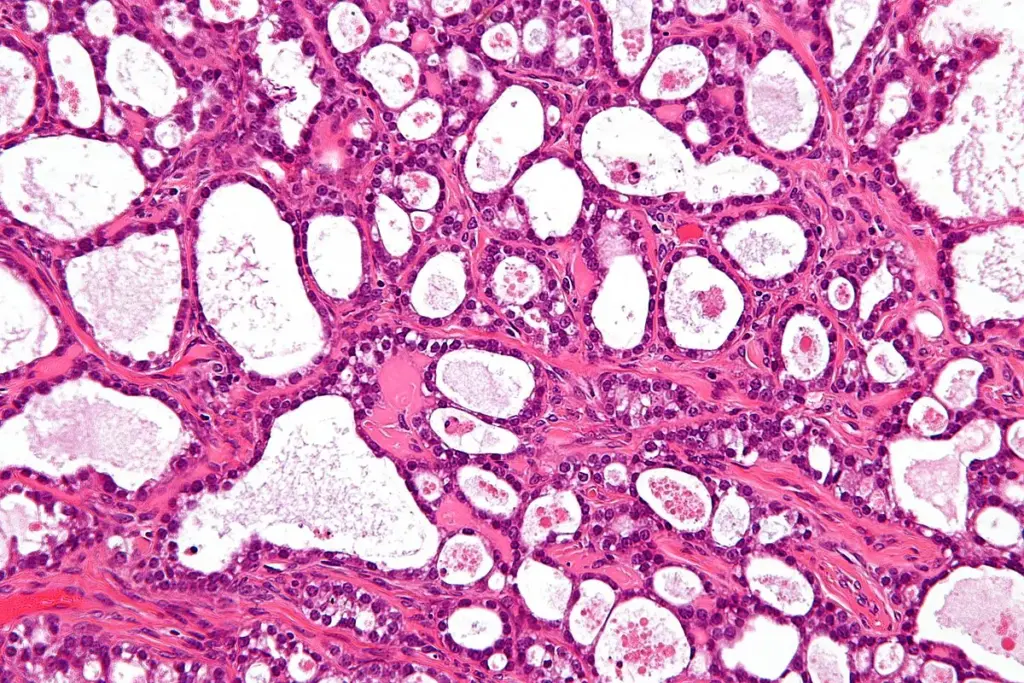

Mechanisms by Which Ginger May Target Ovarian Cancer Cells<SEP-1160_image_3>

Recent studies have looked into ginger’s ability to fight ovarian cancer cells. We can see how ginger fits into a treatment plan for ovarian cancer by exploring its properties.